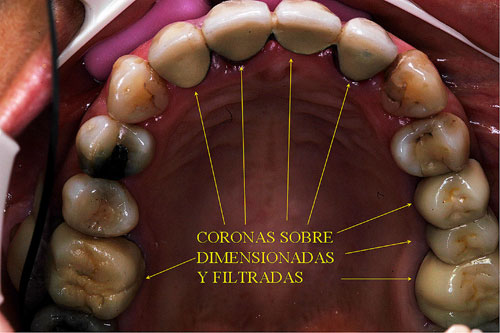

RESUMEN Mostración del Protocolo en R. O. y su desarrollo clínico. DESARROLLO Quienes realizamos Rehabilitación Bucal Integral desde muchos años atrás, siempre hemos buscado un protocolo coherente que nos permitiera ordenar el pensamiento cuando nos encontramos con aquellos caóticos casos donde marearse en la resolución es fácil y frecuente. PROTOCOLO DE ALONSO Sintéticamente consiste en otorgar al Sistema en primer término: Desoclusión en Lateralidades y Propulsiva de los sectores posteriores, mediante la construcción de la Guía Anterior tanto en los Provisorios como en los Definitivos, basados en el Encerado de Diagnóstico. PROTOCOLO PRÁCTICO (BASADO EN D.A.T.O.) Diagnóstico: clínico, radiográfico (donde no es necesario extenderse) y de laboratorio, donde mediante un encerado diagnóstico y otro de trabajo, conoceremos la fiel réplica de la boca del paciente antes de destruirse y los medios para reconstruirla basados en los procedimientos que podemos realizar en la cera. PRESENTACIÓN DEL CASO Se presenta la paciente derivada por un compañero a fin de consultar acerca de un primer molar superior izquierdo, a quien el Periodoncista aconsejaba realizar una radectomía debido a la pérdida ósea distal que dicha raíz presentaba. Dicha observación hace que decidamos tomar una actitud más conservadora, explicando al enfermo las razónes etiológicas de la pérdida ósea, y aconsejando quitar dicha funda para colocar una provisional morfológicamente correcta, y simultáneamente re-endodonciar y realizar la terapia básica periodontal. Visión Global del Caso Se observa a la inspección clínica y radiográfica, varios puentes fijos filtrados, como así también amalgamas de plata recidivadas. Inversión de la Curva de Wilson.(2º Elemento a nuestro alcance para obtener Desoclusión Se procede entonces luego de realizar los correspondientes modelos de yeso mediante impresiones precisas de alginato con cubetas Rim Lock, a tomar un registro cráneo maxilar mediante un arco facial estático (Artex) que nos permita montar el modelo superior respecto del Plano de Frankfurt con el punto Gnation de referencia. Luego, haciendo uso de las Laminillas de Long , (buscar referencias en el libro del Dr. Alonso o bien en múltiples publicaciones personales en Gaceta Dental o Maxillaris, como así también en mi propia web: en los artículos : RELACIÓN CÉNTRICA o AJUSTE OCLUSAL, BASES FILOSÓFICAS DE UNA OCLUSIÓN ORGÁNICA), (www.dracuna.com o www.oclusión.es,) . Procedemos a obtener el Registro Inter Maxilar de OCLUSIÓN EN RELACIÓN CÉNTRICA, mediante el cual, montamos el modelo inferior respecto del superior. Montamos así, en un Artex totalmente ajustable, pués no contábamos en ese momento con ningún semiajustable disponible,(ya que estaban todos ocupados), ajustando el Ángulo de Bennet y la Inclinación de la Trayectoria Condílea en gradaciones personalizadas mediante registros de Propulsión y Lateralidades). Procedemos entonces al estudio de los modelos. DIAGNÓSTICO GENERAL Disfunción oral generalizada, provocada por alteraciones en la Oclusión, en la Operatoria Dental, en la Endodoncia, en la Periodoncia y en la Prótesis realizada en esta boca a través de los años. Filtración generalizada de fundas. DIAGNÓSTICO PROTÉTICO OCLUSAL Carencia de guía canina. Carencia de alineación tridimensional en guía anterior. Carencia de curva de Wilson. TRATAMIENTO SUGERIDO 1-Encerado Progresivo de Diagnóstico y Trabajo de Peter K. Thomas. HEMOS OBTENIDO: D.AT.O Hasta aquí, hemos solo observado los elementos de diagnóstico clínicos, radiológicos y de laboratorio, como para comenzar a trabajar. AUTOR: Colaboración: CASO PRESENTADO EN LAS SESIONES CLÍNICAS DEL ILTRE. COLEGIO DE DENTISTAS DE MÁLAGA. Ratificación del Protocolo en Rehabilitación Bucal a pesar de las incidencias propias de cada caso clínico. A propósito de un caso.

Observada la pieza clínica y radiograficamente, podemos ver una corona excesivamente sobredimensionada sobre un molar deficientemente endodonciado, que no solo muestra la pérdida ósea distal de la raíz en cuestión, sino también y producto de la mala endodoncia, un granuloma en la raíz mesial y en la furca.

Evidente Sobre Dimensionamiento Coronario

Aconsejamos a la paciente realizar un estudio de toda la boca, ya que el molar en cuestión constituía apenas una muestra más de una odontología parcial, iatrogénica, y mal llevada, durante muchos años.

Endodoncias Defectuosas/Carencia de Refuerzos Intradentarios/Coronas Sobre Dimensionadas/Reabsorción Ósea